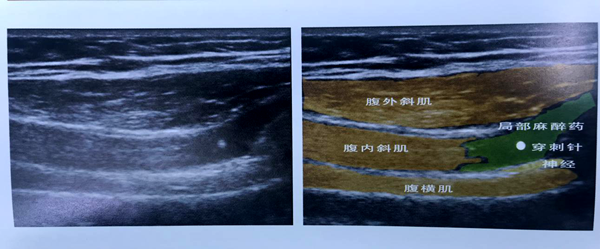

麻醉医生团队在B超引导下行神经阻滞

髂腹股沟-髂腹下神经阻滞B超解剖图

在孙志华主任的主持下,麻醉科各级医生积极参与麻醉前讨论,为该患者制定了一套最佳的麻醉方案:非插管全麻+超声引导下神经阻滞。腹股沟区的神经支配主要有髂腹股沟,髂腹下神经和生殖股神经,如果希望术中无痛和术后镇痛均需要阻滞这些神经。据了解,该神经阻滞传统上曾使用筋膜平面触觉穿刺技术,但由于盲探操作,常导致阻滞失败和并发症。随着超声在麻醉操作中应用愈趋成熟,超声在区域麻醉阻滞中发挥着重要作用。麻醉医生要想做好神经阻滞必须对手术区域的神经支配及走向结构清晰,在超声下监测到神经和周围组织,显示穿刺针和局部麻醉药在神经周围的扩散,减少穿刺并发症和神经损伤,增加阻滞成功率。因此可视化超声也被称为是麻醉医生的“第三只眼”。